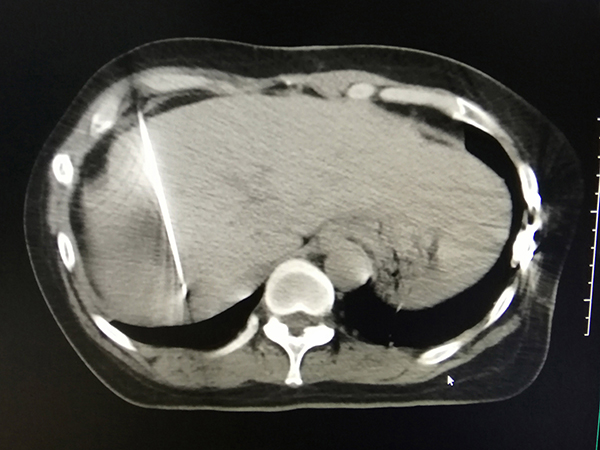

卢女士不幸罹患结肠癌,手术切除后再次发生肝内转移,经多程化疗后肿瘤明显缩小,但肿瘤靠近血管,手术切除风险大且费用较高。2020年10月28日下午,在肿瘤科主任鲁培博士的带领及李竟长副主任医师的积极协调下,肿瘤科介入团队郭旭飞副主任医师和石周主治医师经过反复讨论,并与病人深入沟通后,最终制定了肝转移瘤射频消融术的治疗方案。历时1小时,手术顺利完成,患者取得良好的治疗效果。

治疗后